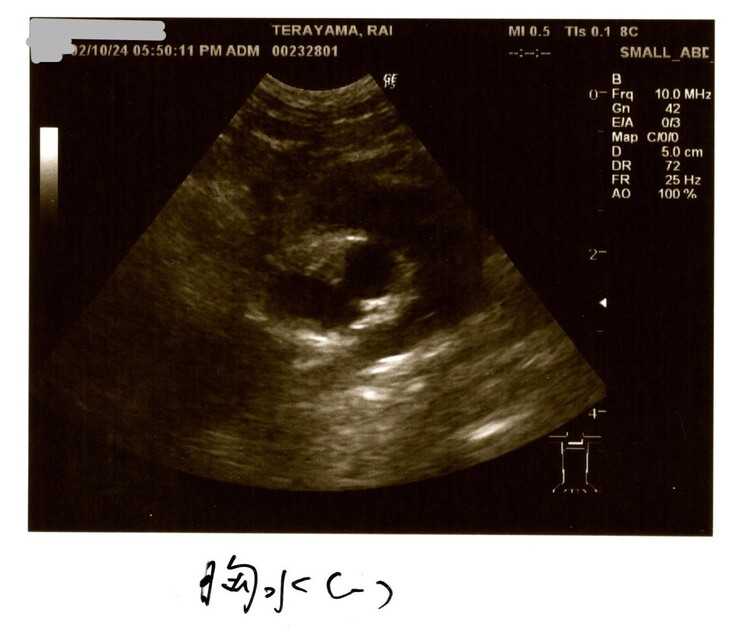

2/10検査結果

2/10はらいくんの2度目の検査結果を聞きました。

何と検査結果は全て改善していました!

血液検査も貧血や黄疸は改善!

油断はもちろんできないけれど、基準値に近づいているものもあり✨

炎症マーカー(血液検査の炎症反応)

改善はしてきていますが、まだまだ高いのでらいくんは辛かったのだと思います。